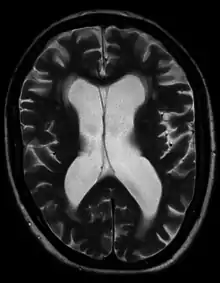

- Normal pressure hydrocephalus (NPH) is a particular form of chronic communicating hydrocephalus, characterized by enlarged cerebral ventricles, with only intermittently elevated cerebrospinal fluid pressure. Characteristic triad of symptoms are; dementia, apraxic gait and urinary incontinence. The diagnosis of NPH can be established only with the help of continuous intraventricular pressure recordings (over 24 hours or even longer), since more often than not instant measurements yield normal pressure values. Dynamic compliance studies may be also helpful. Altered compliance (elasticity) of the ventricular walls, as well as increased viscosity of the cerebrospinal fluid, may play a role in the pathogenesis.[32]

- Hydrocephalus ex vacuo also refers to an enlargement of cerebral ventricles and subarachnoid spaces, and is usually due to brain atrophy (as it occurs in dementias), post-traumatic brain injuries, and even in some psychiatric disorders, such as schizophrenia.[33] As opposed to hydrocephalus, this is a compensatory enlargement of the CSF-spaces in response to brain parenchyma loss; it is not the result of increased CSF pressure.[33]